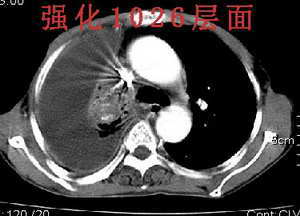

男,76岁,因心累,气紧加重,伴吐白色沫哝痰,偶尔有低烧,无盗汗。{门诊患者未见其它检查}

右肺上叶私有肿块,其内见条状 点状钙化,上叶后段支气管有阻塞征象,纵隔内见淋巴结影,大量胸水,陈旧性结核,肺癌不排除.

病灶在右上叶支气管的后段旁,成类圆形,约2.3厘米大小,其内见钙化密度区,病灶平扫为77,强化为87.左肺上叶尖后段沿血管支气管分布见小结节.我认为右上叶后段支气管开口有截断.我首先考虑是右中央型肺癌伴右恻大量胸腔积液,但左肺的病变我真的有的不好解释,希望各位战友继续讨论,不对之处望指出!!谢谢!!!

右肺毁损萎陷,其内可见钙化灶、残存空腔及支气管影。左上叶可见多发小结节影。纵隔左移,其内未见肿大淋巴结。右侧胸腔大量积液。考虑:肺结核并右肺毁损;右侧胸腔大量积液。

右侧大量胸腔积液伴右肺压迫性肺不张,上叶内是不是结核灶?

右上叶后段开口处可见约3cm·3cm大小的肿块,边缘较光滑,无明显分叶且有钙化,右上叶支气管后壁受侵不明显,加上左上叶病灶。我首先考虑肺结核,胸腔积液。右肺不张。还是建议支气管镜检查,或者胸水检查。

右后段处示一肿块但无明显肺癌强化方式,其内尚见钙化,胸膜亦无结节样增厚,再加上左肺结核表现(支血束结节样增粗不确切),则更支持结核伴大量胸液表现。